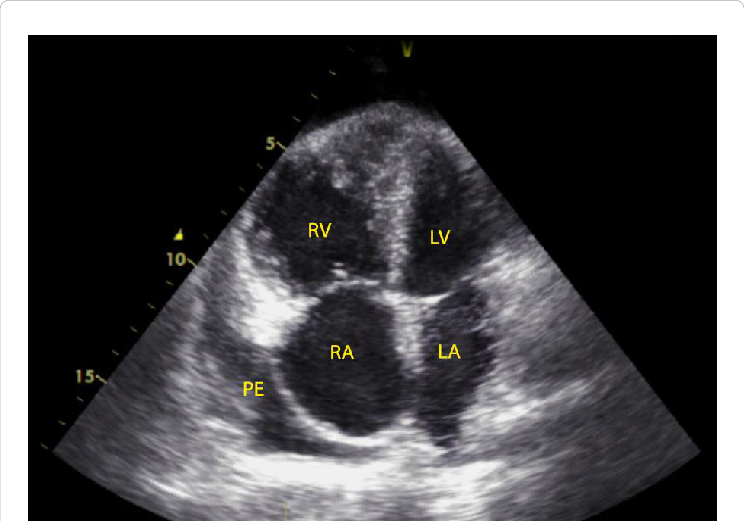

7/ TTE provides non-invasive assessment of right heart structure and function in PAH. Findings of the 3 Ss can guide differential diagnosis and assessment of PH severity.

1⃣Size – RV dilation/ RV shape

2⃣Squeeze – RV contraction

3⃣Smush – Interventricular septal flattening